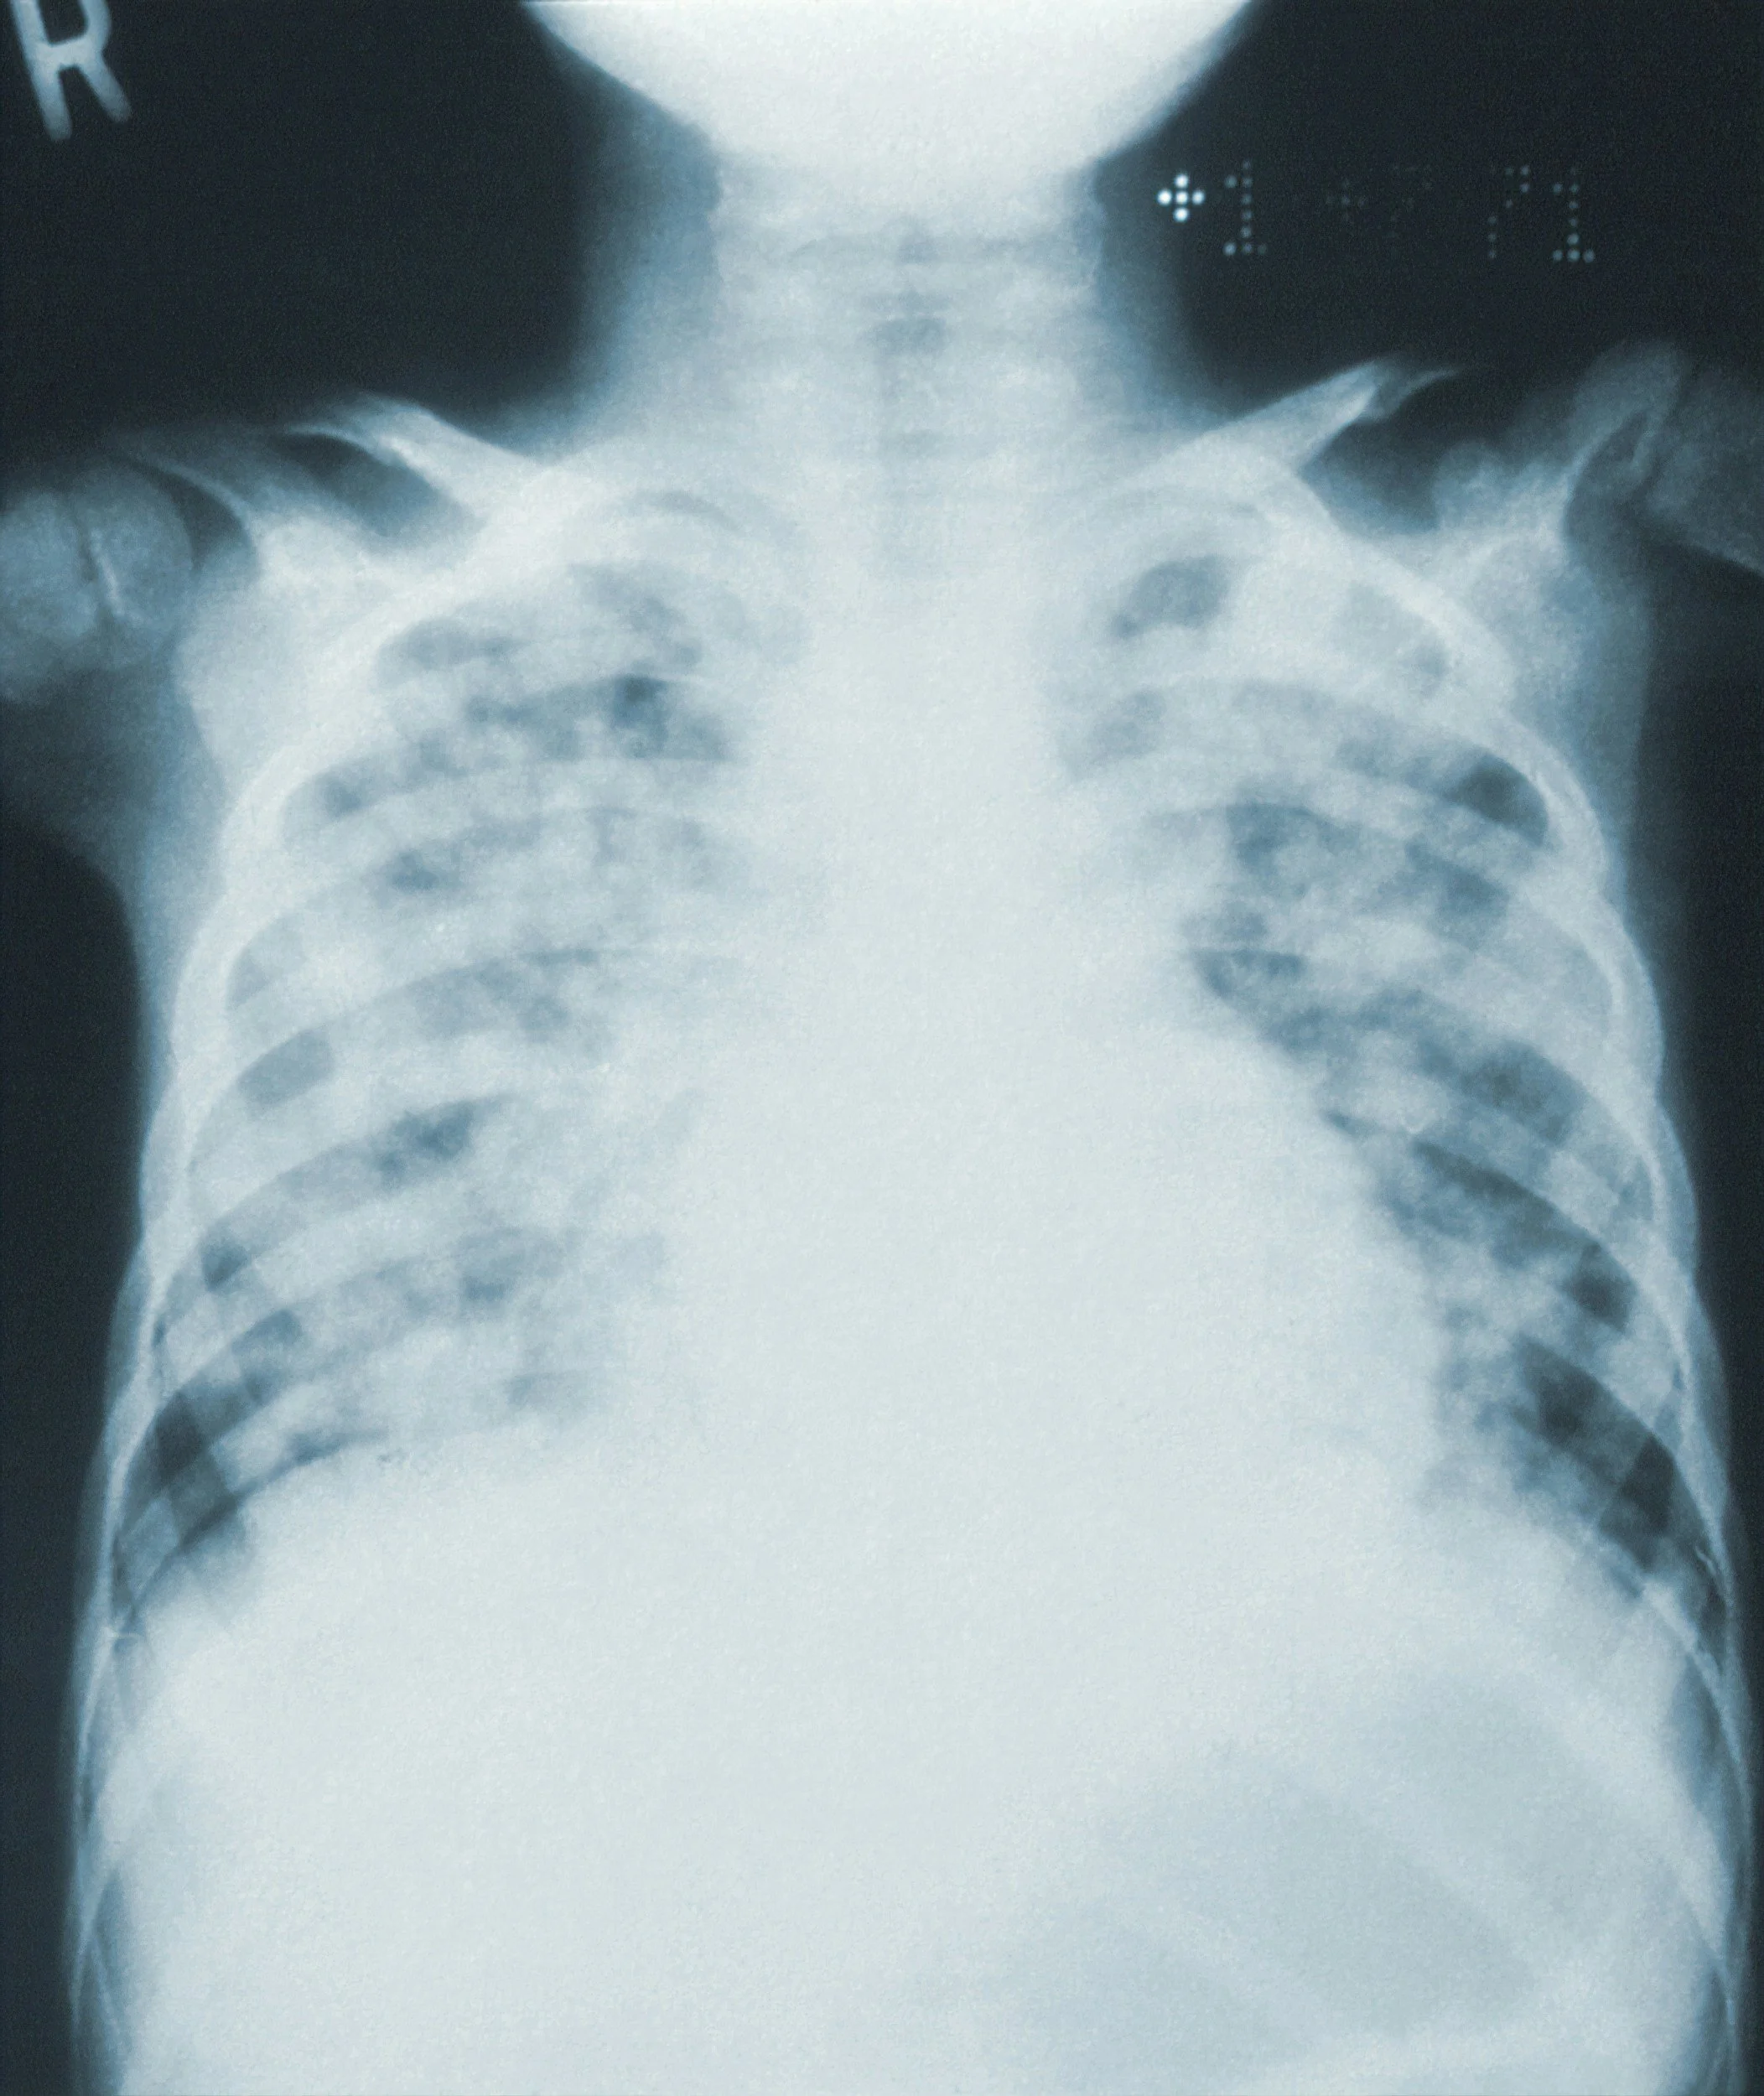

When you hire a domestic worker in the Philippines, standard "medical clearance" is the industry baseline. However, medical data shows that standard frontal chest X-rays miss up to 20% of lung pathologies. MaidProvider.ph, in partnership with Hi-Precision Diagnostics, has re-standardized the PA + Lateral X-ray protocol—the first and only household staffing agency in the Philippines to mandate dual-view screenings for 100% of applicants.